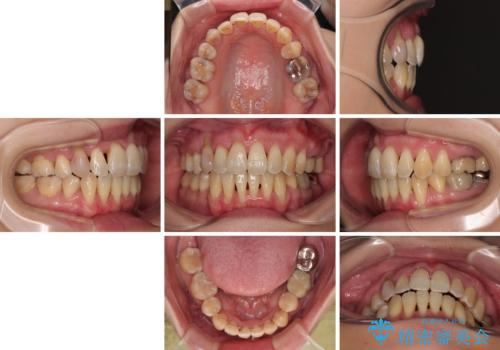

歯根露出が顕著であったため、歯の移動は早く、スムーズに治療を終えられるかと思いましたが、歯槽骨が硬く、治療は長期間に及びました。

過剰に力をかけ続ける事態となり、一部の歯では変色したり、神経が失活したりとトラブルが続きました。

それでも当初とは比べものにならないほど、綺麗な歯列に仕上げることができました。